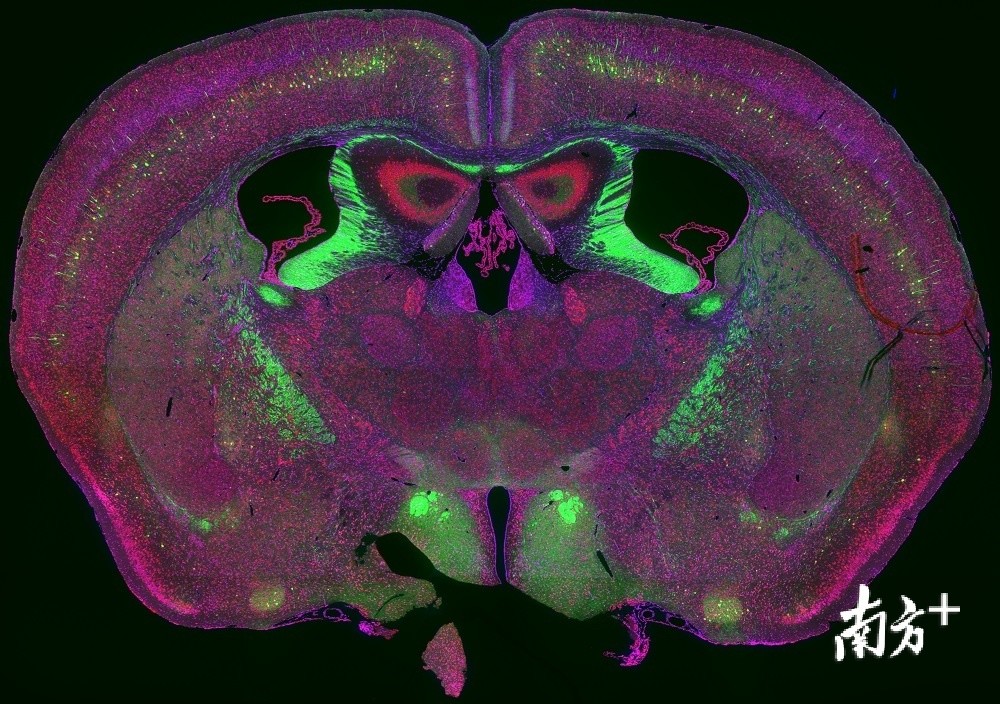

破译大脑运转密码,深圳先进院完成世界首幅猴脑全脑图谱